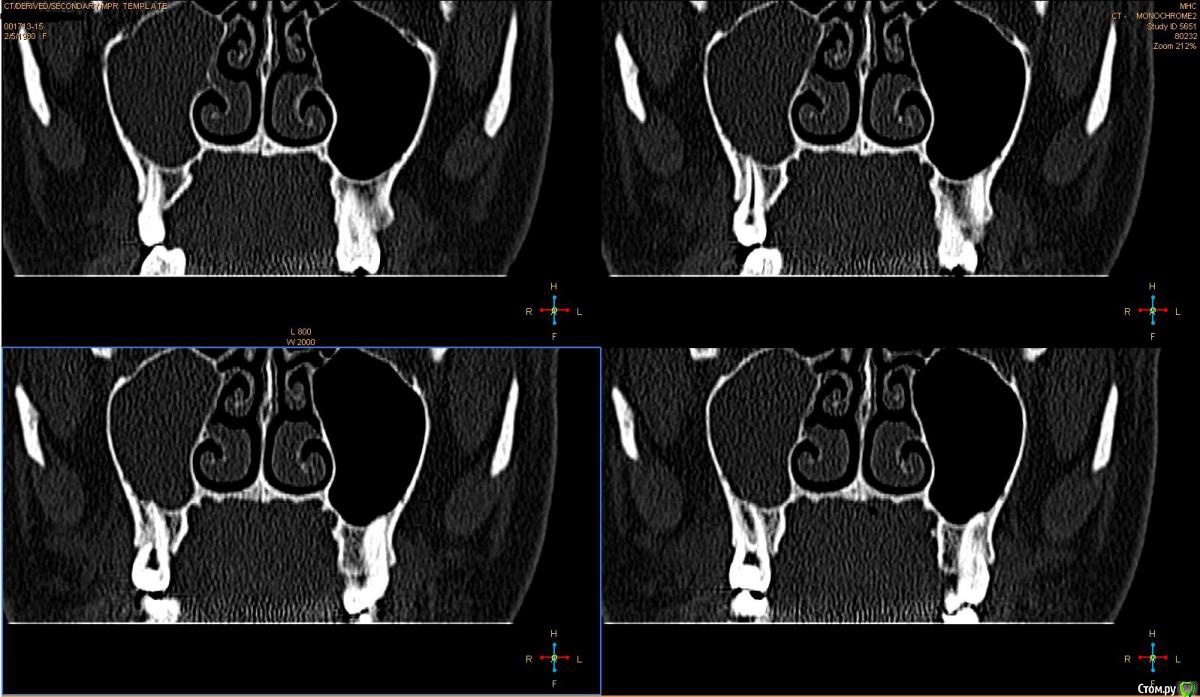

Лисица Опубликовано 26 июля, 2015 Автор Поделиться Опубликовано 26 июля, 2015 (изменено) Вы же не думаете, что Вам назначат а/б терапию по интернету? Я просто не знаю, исходя из каких показателей она назначается. Поэтому осведомилась на всякий случай. Итак, сходила я сегодня на КТ. И по ходу мне сделали что-то не то... Когда я обратилась в клинику, я уточнила, что мне нужно КТ для эндодонтии, чтобы видно было каналы, с достаточным разрешением, чтобы было видно зубы и их корни, входящие в верхнечелюстной синус. Администратор клиники уточнила у врача и сказала, что мне нужно заказывать не КТ верхней челюсти, а КТ пазух. У рентгенолога я также повторила все описанное, рассказала, что при лечении каналов вчера была продырявлена пазуха, уточнила, будут ли видны как следует зубы и их каналы, меня заверили, что "все будет". Причем у врача, судя по описанию на сайте клиники, была ординатура по хирургии в медико-стоматологическом университете, так что он, уж наверное, понимал, что мне нужно. В итоге я получила пленку со снимками формата чуть ли не А3 и диск. На пленке все зубы были просто белыми и коронки видны не целиком. Заключение: в правой верхнечелюстной пазухе уровень жидкости, острый правосторонний гайморит.Думала, может в программе можно будет увеличить разрешение. Но похоже, что нет... или я просто ламер? Зубы просто размытые и белые... Прилагаю сделанные мной скриншоты, как мне кажется, наиболее показательные... Если нужно другие "виды", то скажите какие, или такие снимки вообще ни о чем? Программа просмотра называется Philips DICOM Viewer R3.0-SP03. Аппарат был не местный "на голову", а здоровый, куда заезжаешь в лежачем положении. Изменено 26 июля, 2015 пользователем Лисица Ссылка на комментарий

Лисица Опубликовано 26 июля, 2015 Автор Поделиться Опубликовано 26 июля, 2015 Тьфу ты, Акелла промахнулся. Не та сторона в профиль. Вот парочка проекций с нужной больной стороны. Ссылка на комментарий

Лисица Опубликовано 26 июля, 2015 Автор Поделиться Опубликовано 26 июля, 2015 О, кажись я накопала настройки для более-менее понятного отображения Хоть и не уверена, что это то что нужно. Ссылка на комментарий

St. Опубликовано 27 июля, 2015 Поделиться Опубликовано 27 июля, 2015 Гайморит справа есть, и жидкость тоже. Корни этого зуба действительно заканчиваются в гайморовой.Ничего такого страшного, чтоб однозначно удалять зуб я не вижу. С гайморитом - к лорам на лечение.В зубе я бы ещё раз поменяла лекарство на пару недель, пока гайморит не притихнет, потом постоянно пломбировать. 1 Ссылка на комментарий